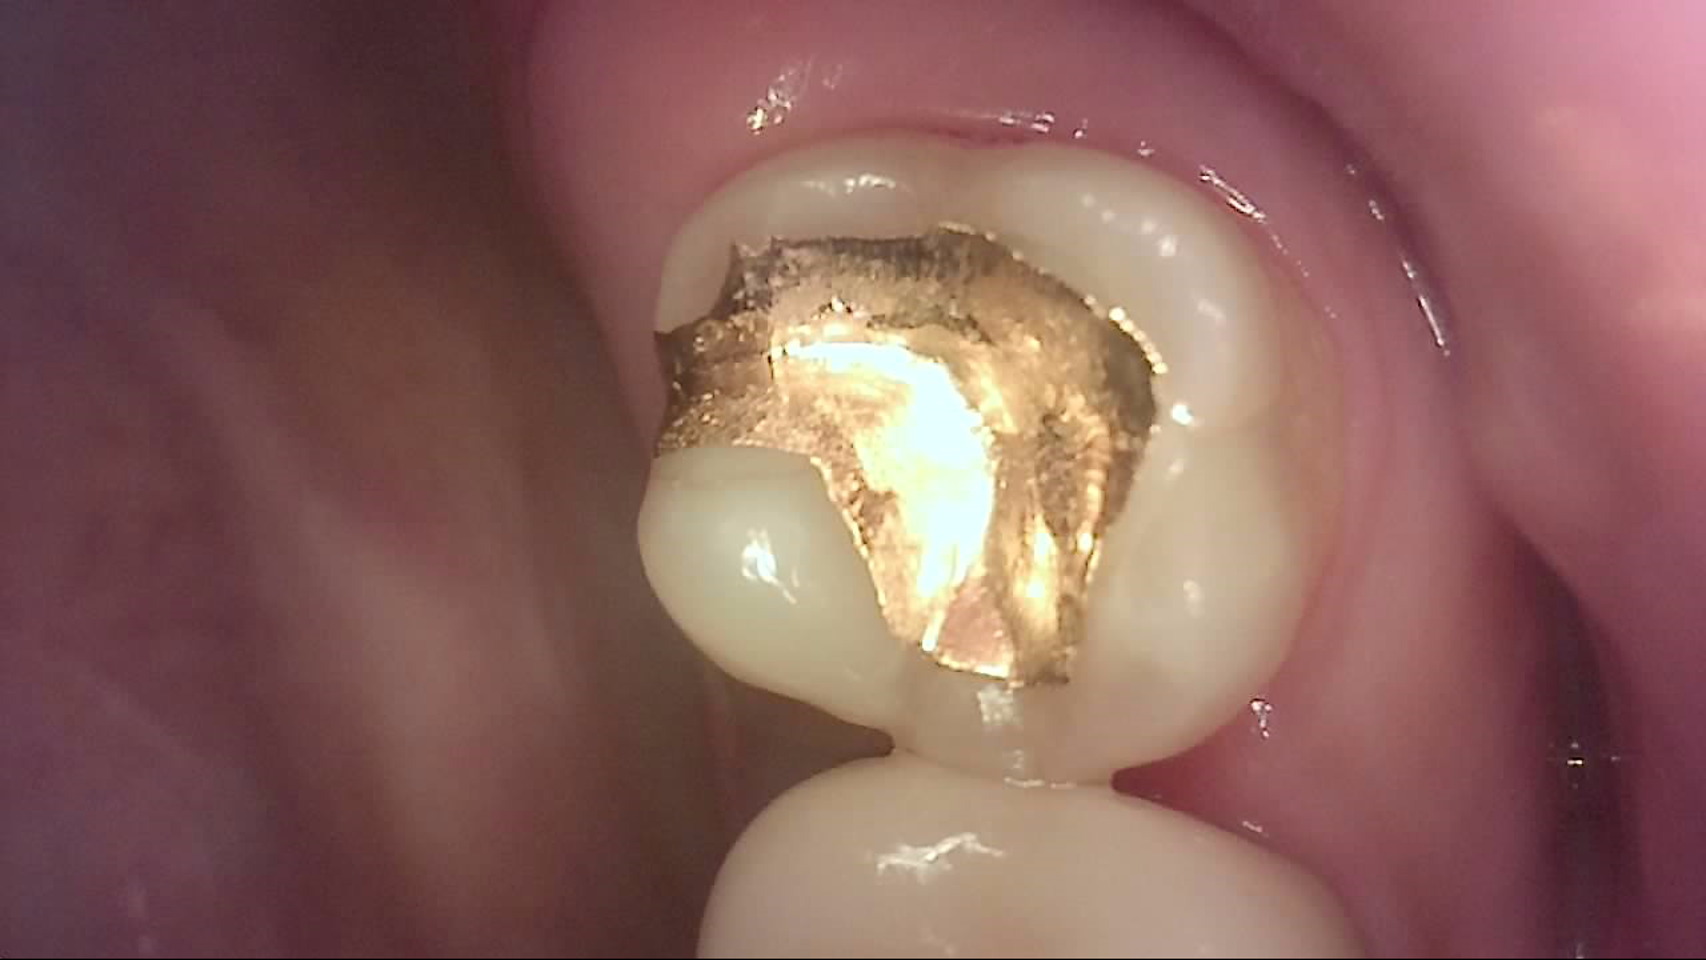

Crack

큐레이캠프로, 큐레이펜씨